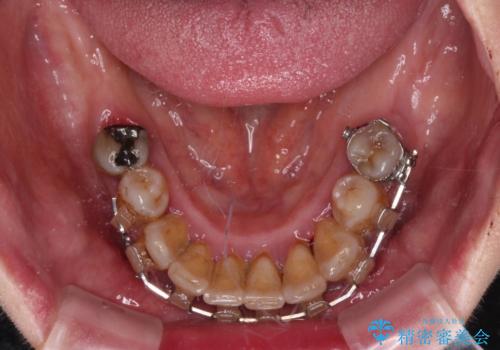

- インプラント治療を前提に下顎の部分矯正を始めたものの、そのまま長い間放置しているとのことで来院された患者様です。

全体的に歯肉が腫れており、歯周病により抜歯をしなければならない歯がある状態でした。

矯正治療を仕上げ、必要に応じて歯周外科処置を行い、適宜インプラントを埋入しながら咬み合わせを回復させていくこととしました。

治療前は磨き残しが多く見られ、全体的に歯肉が腫れている状態でしたが、抜歯の必要な歯を抜いたことで口腔内の環境が改善され、磨き残しも少なくなってきました。